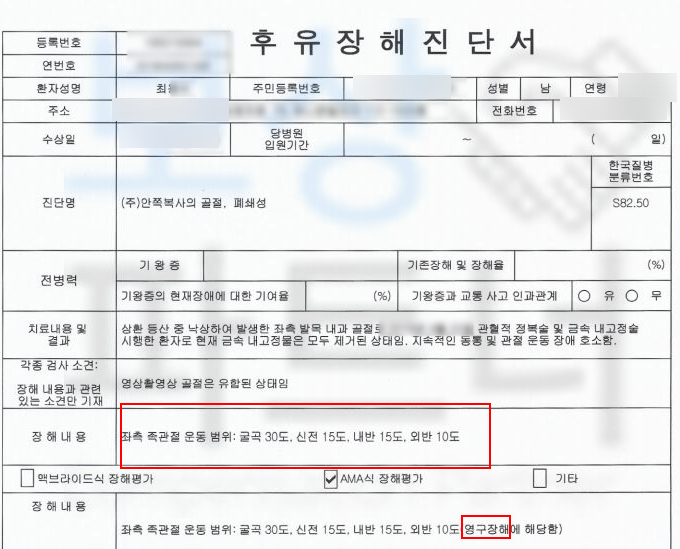

최@@님은 등산 중에 넘어지는 사고를 당하셨습니다.

위 사고로 발목 통증이 계속되자 정형외과에 내원한 의뢰인은

족관절 내과 골절 및 관절 내 유리체에 손상을 입었고 s8250 핀 고정술을 받아야 했습니다.

보험금 청구를 진행하기 전 의뢰인의 보험증권 분석과 엑스선 사진과 현재 움직임을 파악하여

상해 후유장해 3% 보. 험. 금

청구 가능성을 확인하여 진행했습니다. 의뢰인은 손해보험사에 후유장해 담보 총 23,100만 원 가입되어 있었고

후유장해 평가를 진행하였습니다. 그 결과

족관절의 약간의 장해 5% 해당하였죠.

의뢰인의 복사뼈 골절이 관절면까지 손상되어

5% 영구 장해 지급률 모두! 인정받아 후유장해보험금 1,255만 원 지급받았습니다. 위 보상 사례처럼 여러분도! 상해 후유장해 3% 담보 통해서 후유증 보상받을 수 있습니다.